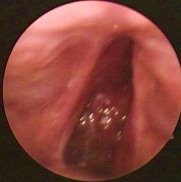

Hình ảnh nội soi tai

Ảnh 8 MN lõm, vàng MSBA. 1912331936 | |